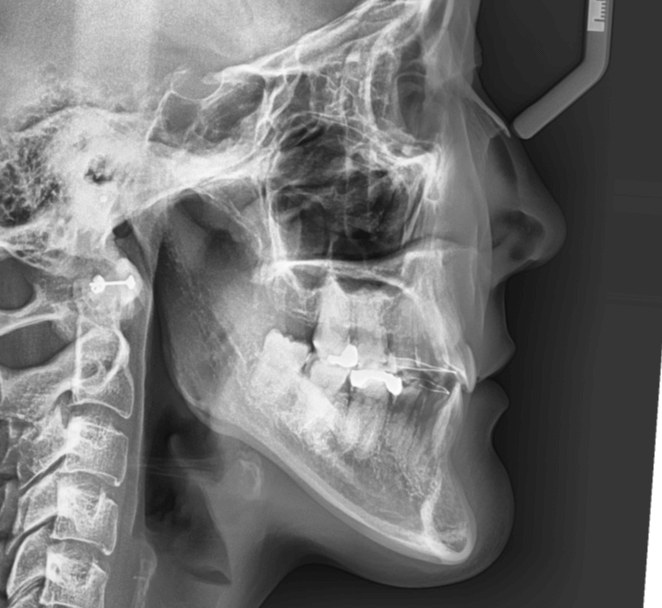

| 年齢・性別 | 15歳の女性 |

|---|---|

| 主訴 | 咬み合わせが逆であること(反対咬合)を気にされて来院された15歳7か月の女性。見た目や機能面の改善を希望されていました。 |

| 治療期間・回数 | 4年4ヶ月・28回 |

| 費用 | 900,000円 |